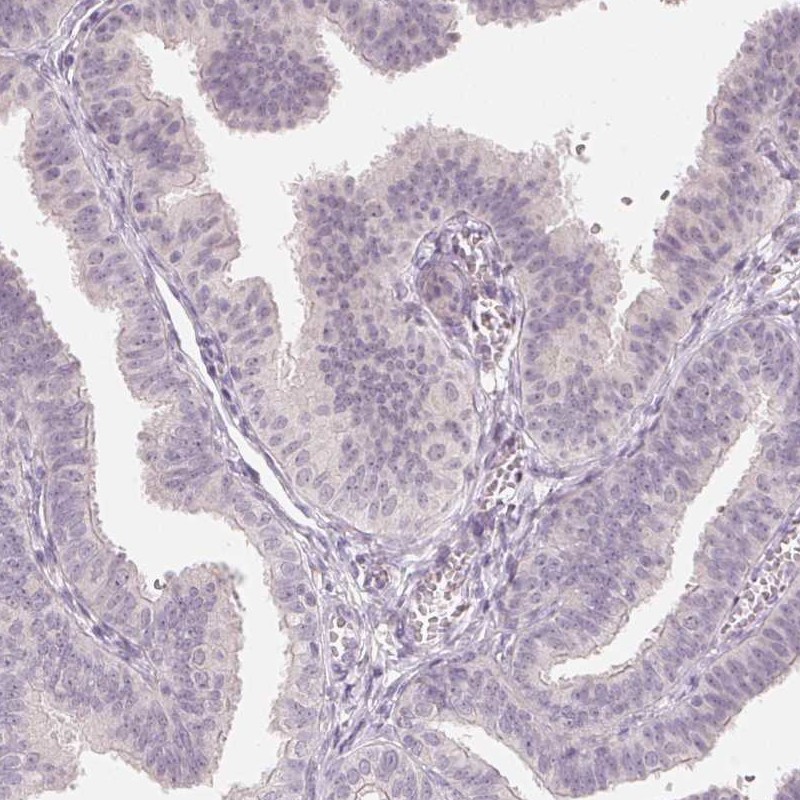

Immunohistochemistry analysis in human testis and fallopian tube tissues using Anti-ANKRD31 antibody. Corresponding ANKRD31 RNA-seq data are presented for the same tissues.